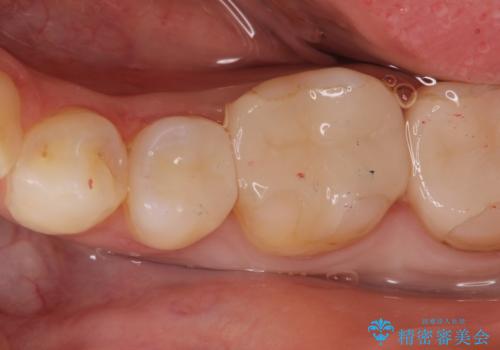

虫歯の治療(セラミックインレー)

- 定期検診にて虫歯が見つかり、セラミックインレーに治療を行っております。

e-max プレスインレーにて修復治療を行っているため適合性及び審美性の高い治療を行うことができます